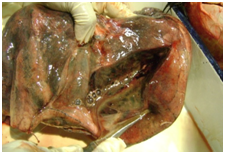

Salient internal findings

Morphology of lungs in ARDS: initially the basic lesion affects capillary endothelium-the damage to the capillary endothelium results in an increased capillary permeability-oedema and fibrin exudation followed by formation of hyaline membranes - composed of necrotic epithelial cell debris and exudative proteins-predominantly fibrin. The other characteristic morphologic feature include inflammatory infiltration of the interalveolar septa.4

From the autopsy findings, supported by the ancillary investigations, it is evident that the unfortunate young patient might have suffered from pneumonitis in the initial phase of his febrile illness. The development of ARDS/sepsis and renal pathology was secondary to pneumonia, the aetiology of which remains undiagnosed. Autopsy of a case of sudden, unexplained natural death is basically a challenge for the autopsy surgeon. In rare cases histopathology and other modern ancillary investigations may give us surprising results that may lead to elucidation of the pathological explanation of the cause of death, as happened in the present case.